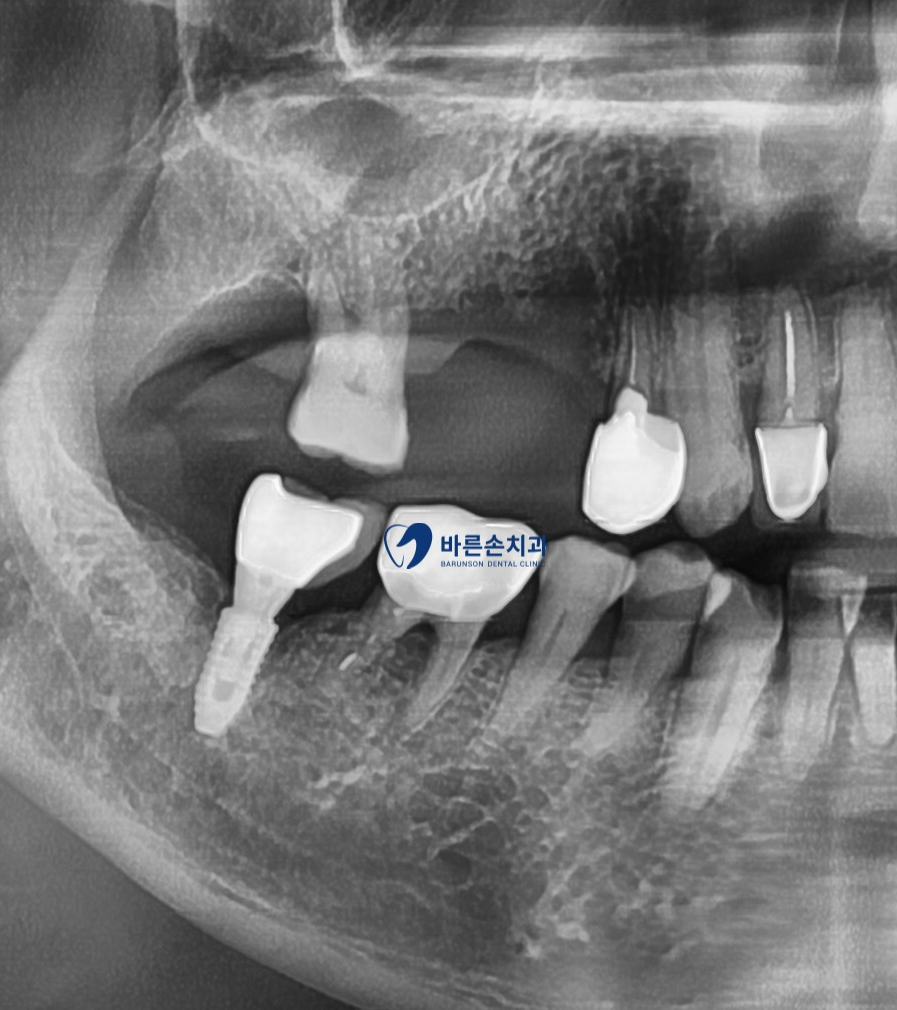

통증의 원인된 치아 발치와 함께 기존에 있던 염증을 깨끗히 제거 합니다

염증으로 인해 치조골 손상도가 높은 케이스라 상악동 거상과 치조골 이식을 동반하였습니다

이로 인해 알맞은 위치에 임플란트가 잘 고정되어져있는게 보이네요^^

이 후 임플란트가 환자분 치조골에 잘 결합되도록 약 3개월의 기다림이 필요합니다